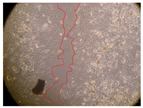

| Representative Image of the Cells at the Initial Moment (0 h) | ||||

|---|---|---|---|---|

![]() | ||||

| 2 h | 8 h | 12 h | 24 h | |

| Control | ![]() | ![]() | ![]() | ![]() |